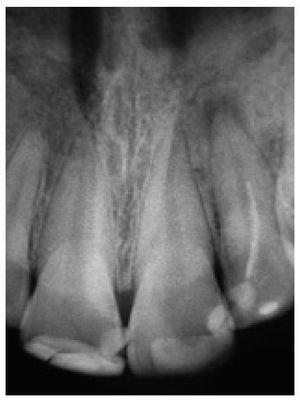

La exploración radiográfica confirmó las zonas de infiltración de caries y asimismo reveló un tratamiento endodóntico incorrecto en el diente número 22, en el que el acceso se había realizado exclusivamente a través de la cavidad de clase III mesial, con la consecuente lesión periapical asintomática (figura 33).

Figura 33 Radiografía del tratamiento endodóntico del diente número 22 con acceso a través de la cavidad de clase III mesial, con lesiones periapicales.